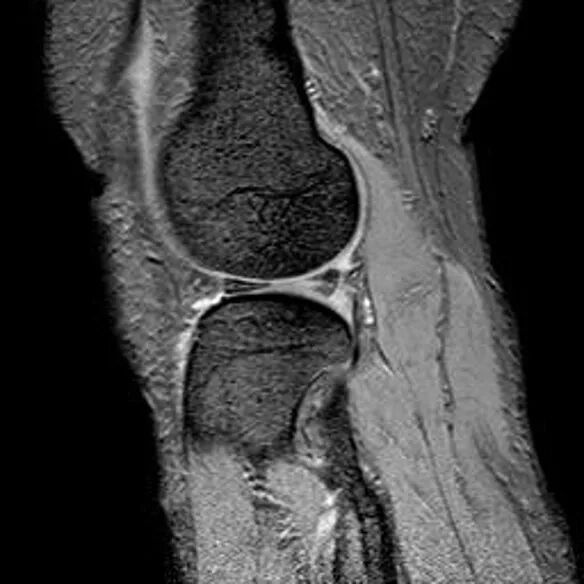

桶柄状撕裂MRI表现

1、宽度减小,在通过半月板体部的冠状面上蝶形消失,同时可见内移的半月板位于髁间窝、交叉韧带旁2、矢状面示残余的前角或后角变小或截断3、半月板前(后)角增宽或双半月板前(后)角征4、双前交叉韧带或双后交叉韧带征

桶柄状撕裂(双后交叉韧带征)

桶柄状撕裂:双前交叉韧带征